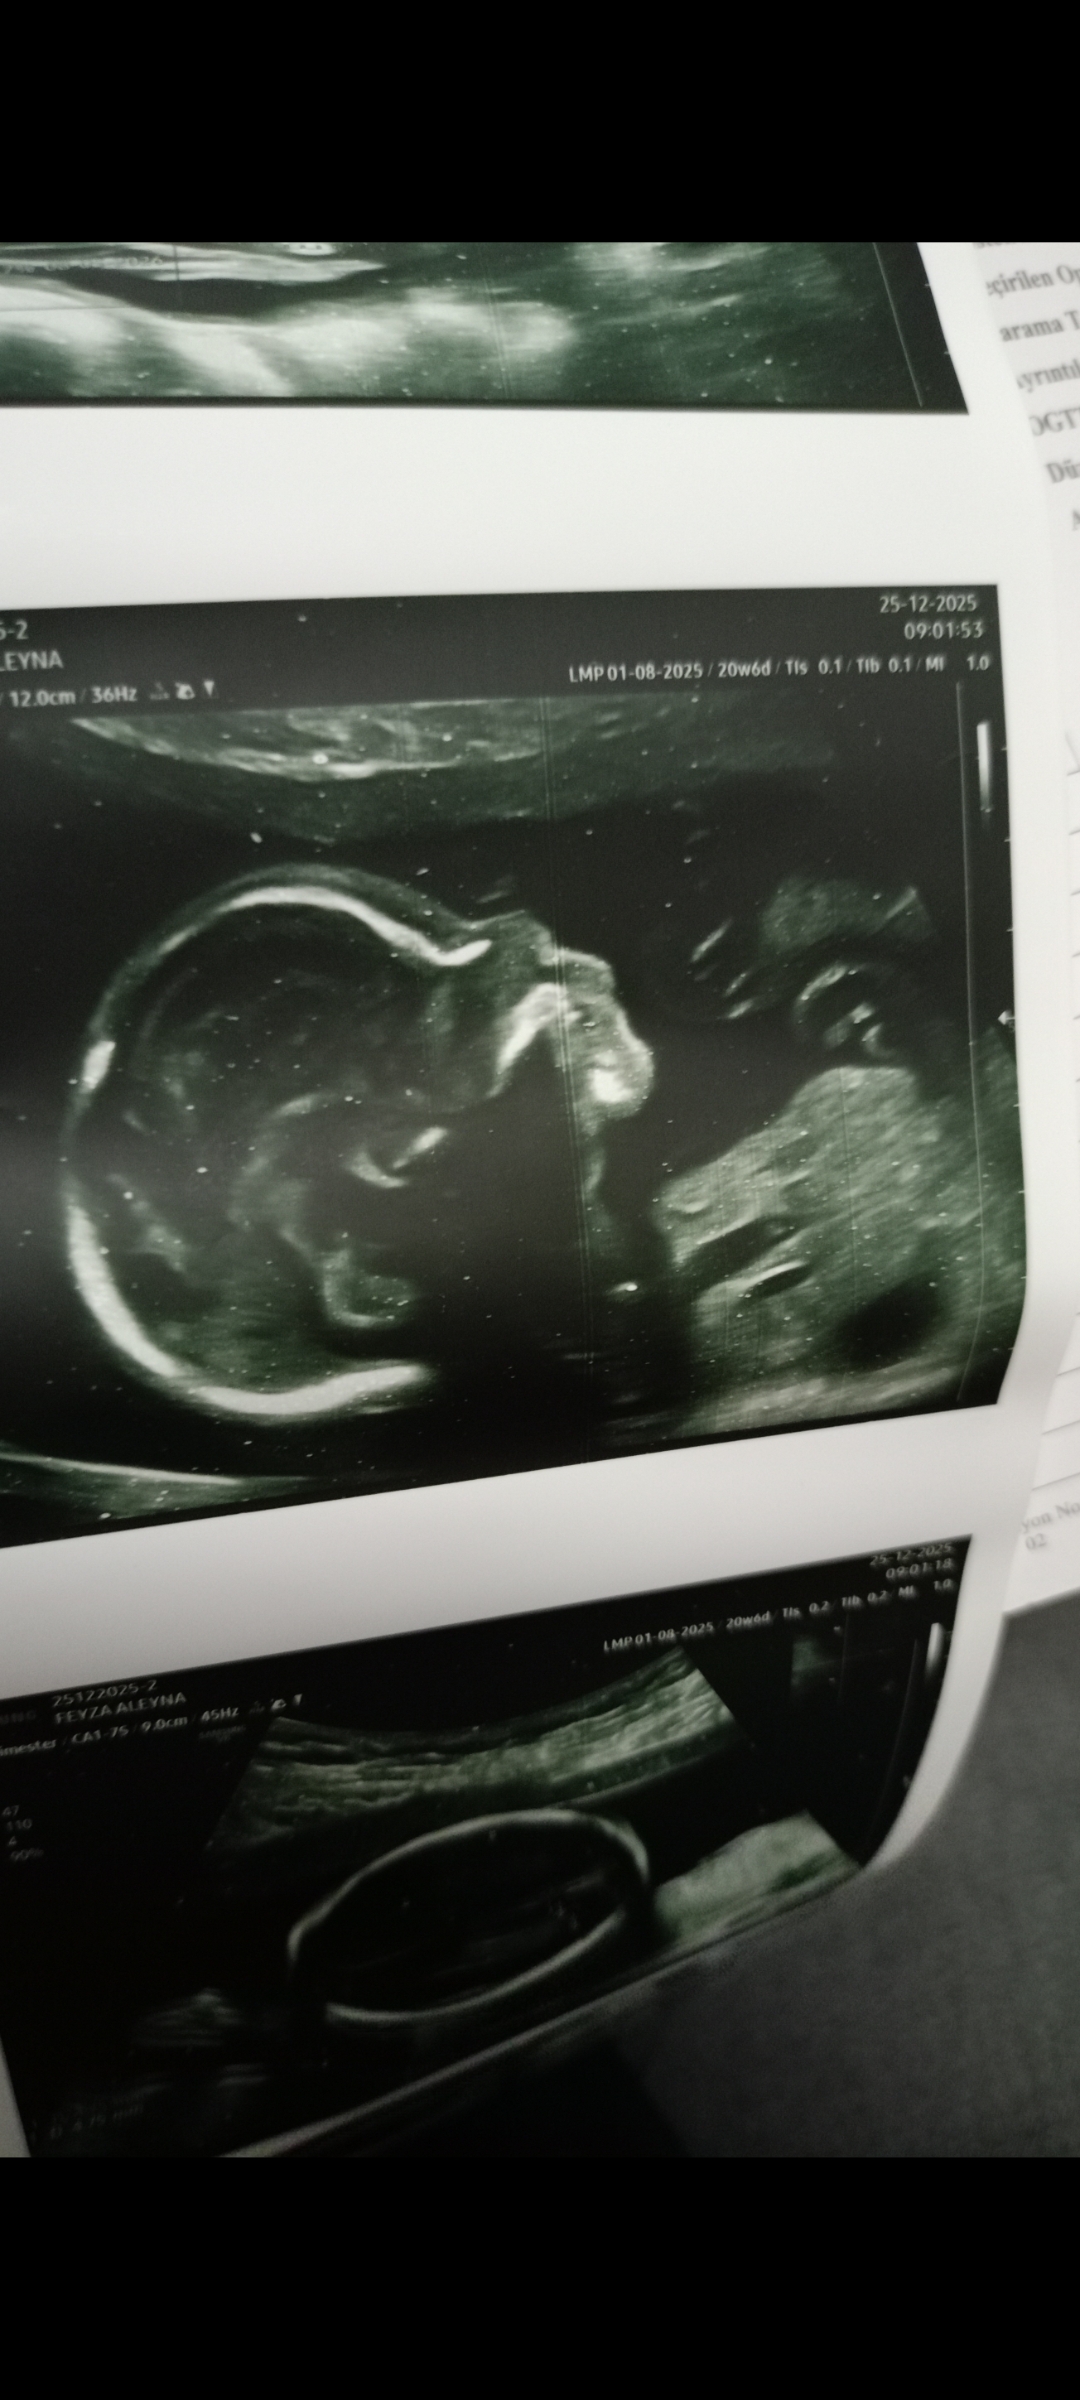

12 haftalıkken erkeğe bebziyor ama eminde değilim dedi 4 kere gittim sonra göstermedi kendini bugün hareketliydi zaten meyve suyu falanda içtim direk gösterdi kız dedi

1000005874.jpg

Tipe bak teyzesi

Ekli dosyayı görüntüle 5724

Ablacım günaydın gösterdi kendini kız olcakmış😄😄😆